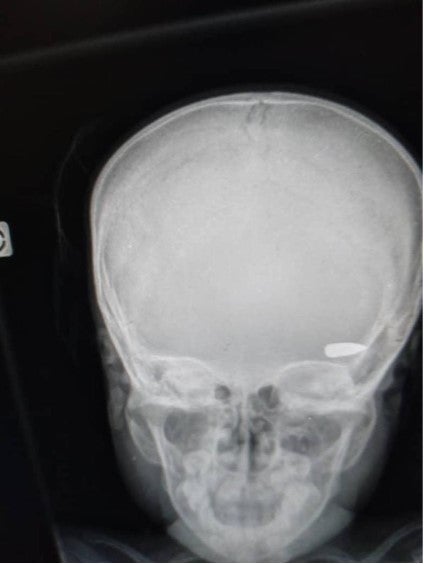

An x-ray image shows a bullet lodged in the head of a child who was hit during a confrontation between criminal groups in the Brooklyn neighborhood of Cité Soleil commune in early April 2023

An x-ray image shows a bullet lodged in the head of a child who was hit during a confrontation between criminal groups in the Brooklyn neighborhood of Cité Soleil commune in early April 2023